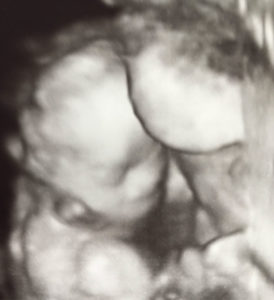

22 Weeks Pregnant!

22-weeks-pregnant-after-reversing-tied-and-cut-tubesI’m now 22 weeks 5 days I’m so happy that Dr Charles Monteith was able to make this blessing come true.

So I want to say thanks again……